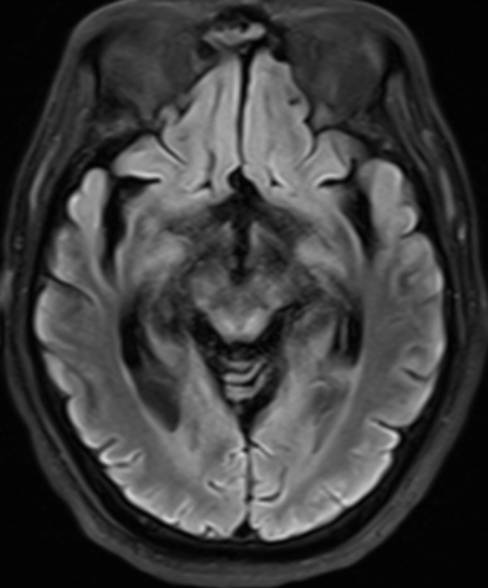

MRI病变评估方法参考既往研究中描述的方案[7]。由两位具有丰富经验的神经放射学家,在未知患者临床诊断的前提下评估双侧大脑区域病变情况,包括额叶、颞叶、顶叶、枕叶、胼胝体膝部和(或)体部、胼胝体压部、基底节区、丘脑、脑干、小脑,共计18个解剖区域。每个脑区采用二分类评分法:0分表示无病变或只有小的局灶性病变;1分表示有较大的病变(累及该脑区体积的30%以上)或弥漫性病变(图1)。

Figure 1. The T2-weighted and diffusion images of a patient

1. 一名患者的T2加权和弥散图像

患者为60岁男性,入院诊断为呼吸心跳骤停(心肺复苏术后)、脑梗死恢复期,入院时双侧瞳孔对光反射消失,图像显示两侧基底节区、丘脑弥漫性缺氧损伤,且脑干出现多发病变,患者出院时仍为植物状态。